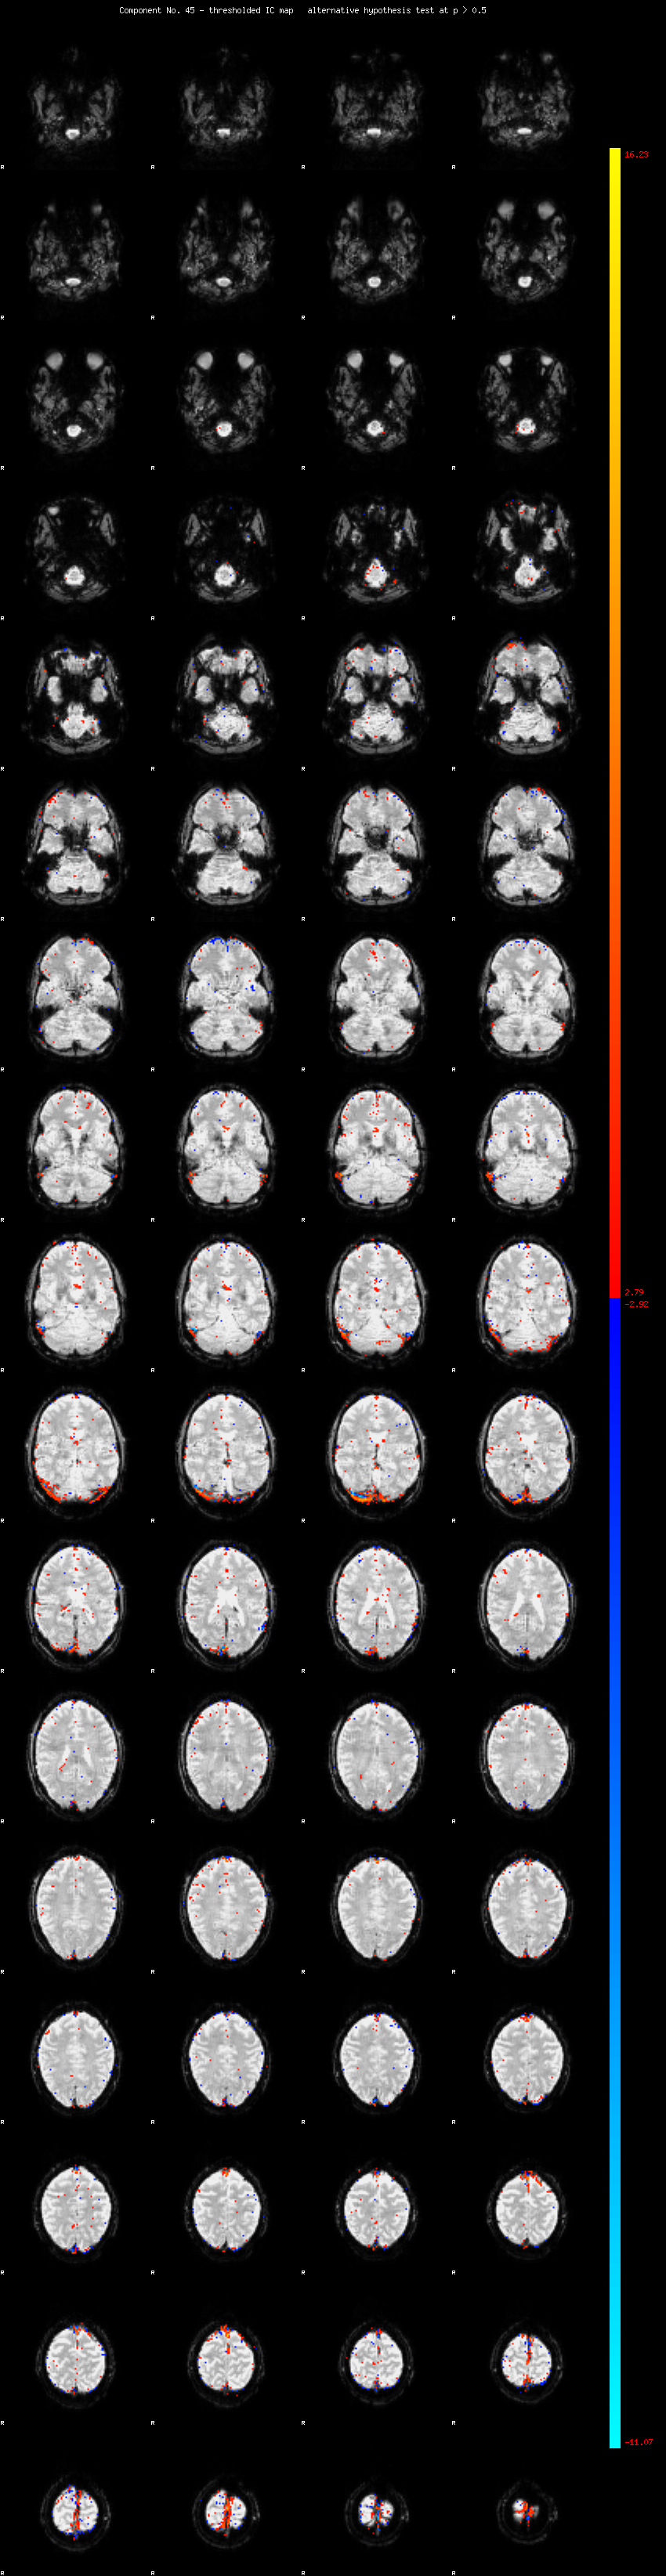

MELODIC Component 45

1.07 % of explained variance;     0.71 % of total variance

MMfit